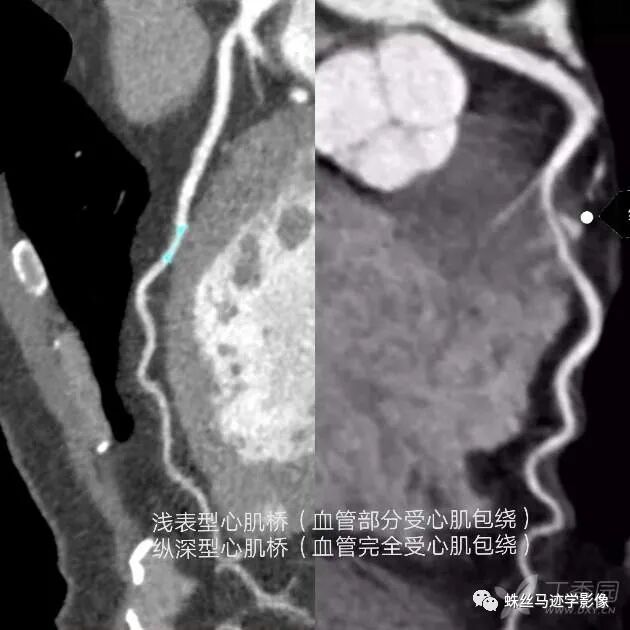

心肌桥/壁冠状动脉:冠状动脉及其分支通常走行于心包膜下方,但有时会以不同的深度在心肌纤维之间走行,然后重新出现在心脏表面,而在心肌纤维内走行的动脉被称为壁冠状动脉 mur alcoronaryartery,MCA),覆盖于冠状动脉上方的心肌称为心肌桥( myocardialbridging,MB)。